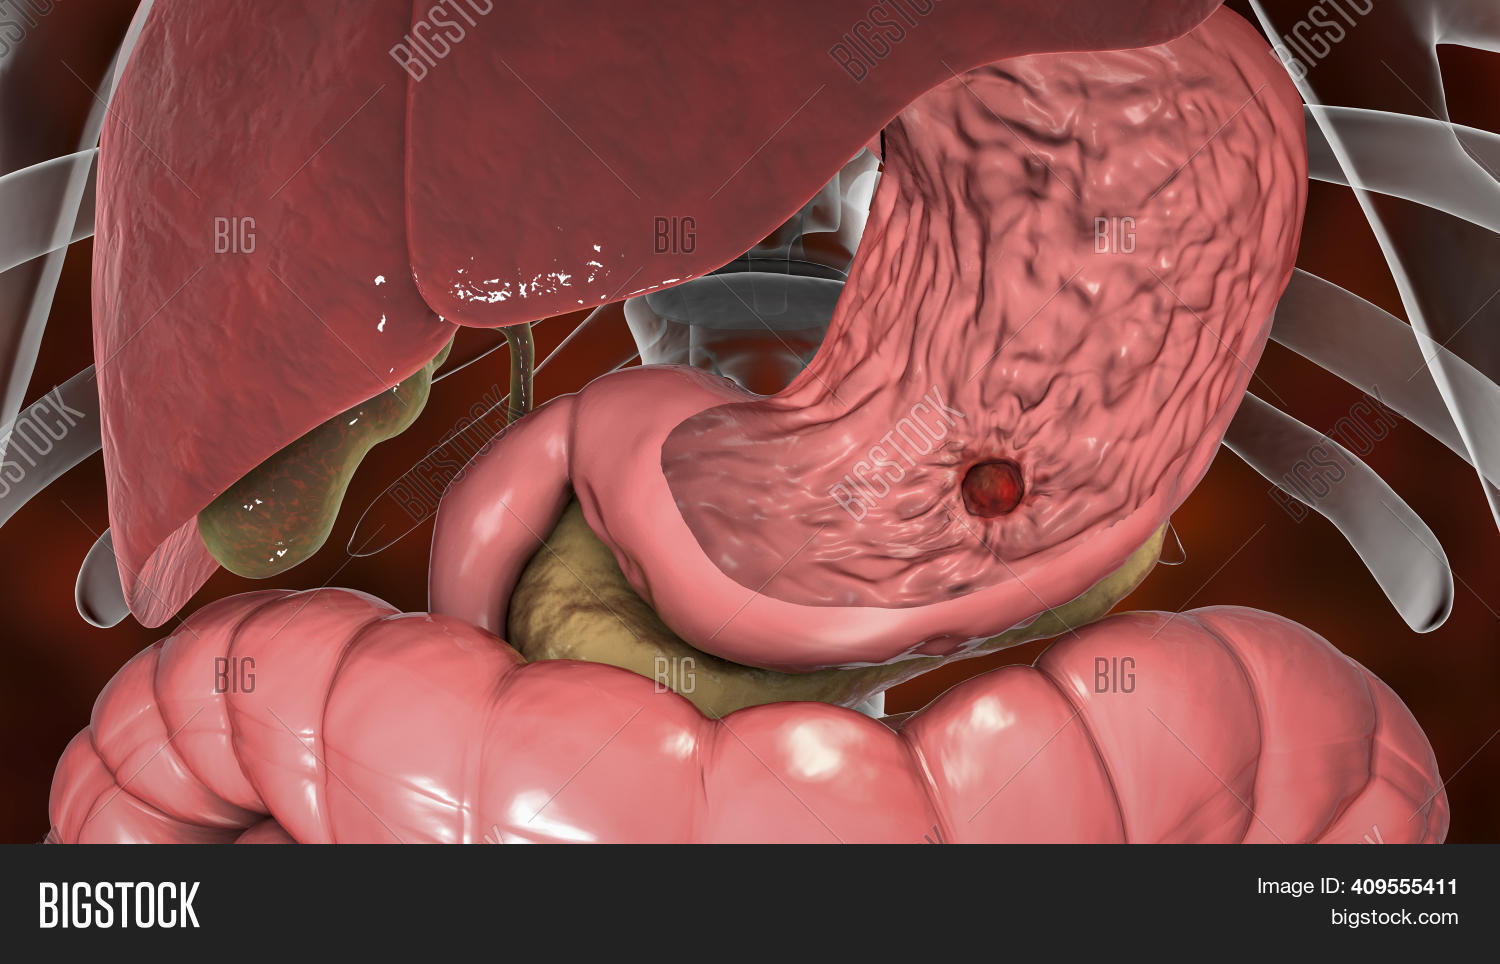

Peptic ulcer, 3D illustration showing organs of digestive system and an ulcer on the stomach surface